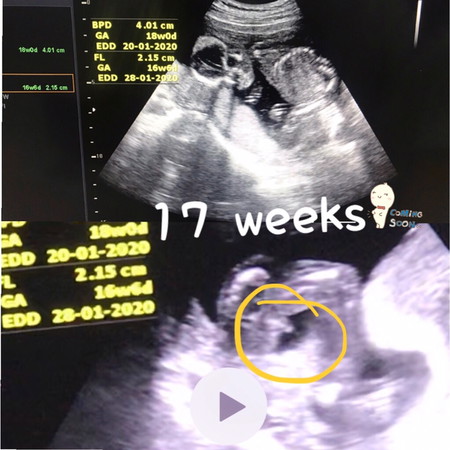

ชายมั้ยค่ะ??

ช่วยดูหน่อยค่ะ หมอบอกอาจจะชายต้องรอซาวน์อีกรอบค่ะ ที่บ้านอยากได้ลูกชายค่ะ 555

แม่มองว่า เพศชายเหมือนกันค่ะ

นั่นน่าจะเป็นจุ๊ดจู๋น้องนะคะ